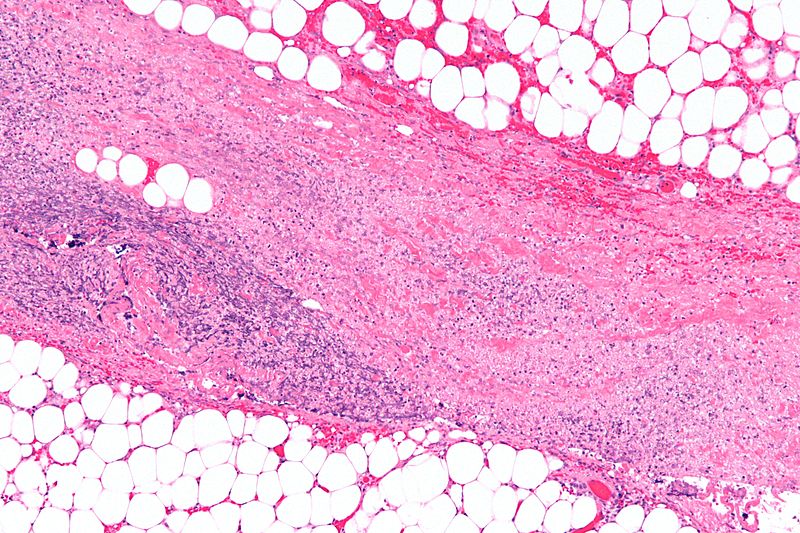

เนื้อเยื่อของผู้มีภาวะ Necrotizing fasciitis

บริเวณสีชมพูตรงกลาง แสดงเนื้อเยื่อที่ตายจากการติดเชื้อ